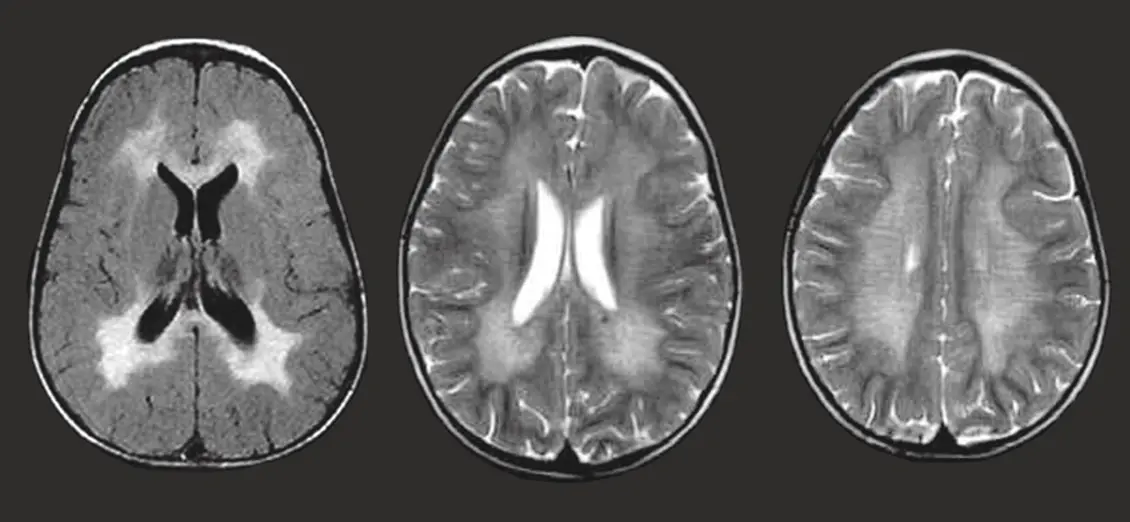

Metachromatic Leukodystrophy

Metachromatic leukodystrophy is a rare inherited metabolic disorder that affects the nervous system. It is caused by a deficiency of an enzyme needed to break down certain fatty substances in the body. As these substances accumulate, they damage the myelin sheath, the protective covering around nerve fibers in the brain, spinal cord, and peripheral nerves. The disease is progressive and …